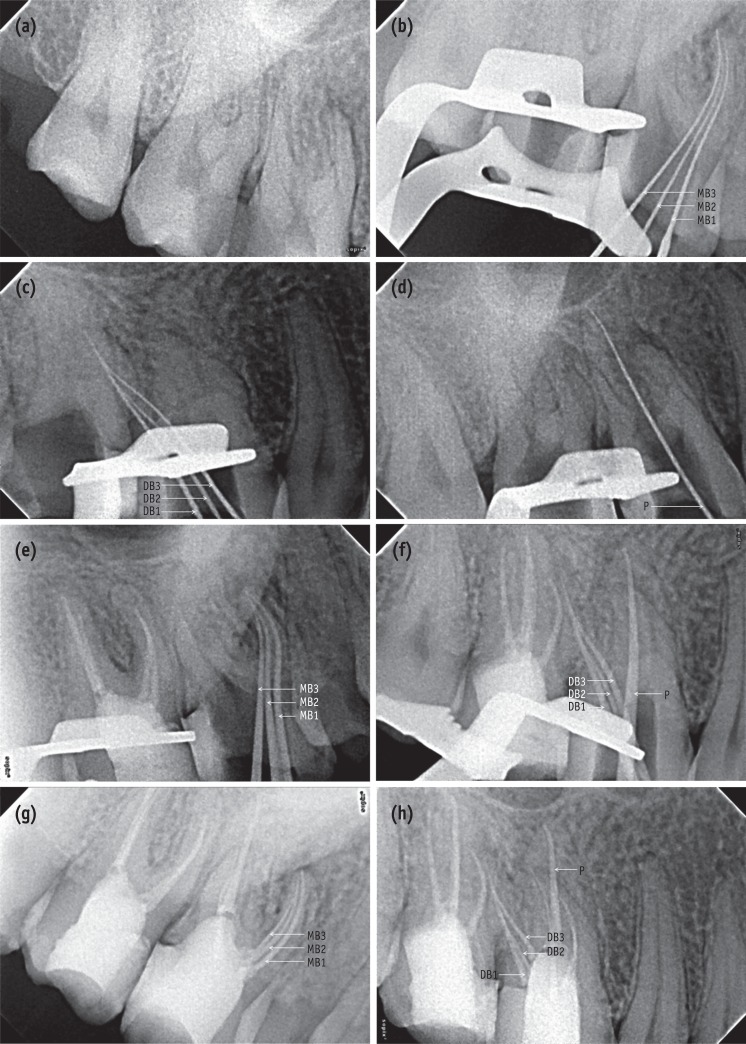

CBCT images of tooth 16. (a - c) Axial sections. CBCT scan images of the maxillary arch at the cervical (a), middle (b), and apical third (c) levels showing three roots and seven root canals (squared area); (d - e) Transverse sections. CBCT scan images of the mesiobuccal (d) and distobuccal (e) roots.

To confirm this rare and unusual morphology, dental imaging of the tooth with the help of CBCT (Carestream CS 9300, Carestream Dental LLC, Atlanta, GA, USA) was planned. An informed consent was obtained from the patient, and multi-slice scans of the maxilla was performed with a tube voltage of 90 KV and a tube current of 15 mA. All measures were taken to protect the patient from radiation. The involved tooth was focused, and the cross-sectional images were obtained in axial, transverse and sagittal planes (Figures 3a - 3e). All images were analyzed with the help of CS 3D imaging software (Carestream Dental LLC). Axial images were obtained at 180 µm thickness and were studied at cervical, middle and apical third of the roots to determine the canal morphology (Figures 3a - 3c). The images revealed that the tooth 16 had three roots and seven root canals (three mesiobuccal, three distobuccal, and one palatal). Transverse section CBCT scanned images of the mesiobuccal and distobuccal root confirmed the canal configurations that were seen in the working length radiographs (Figures 3d and 3e). In contrast, the contralateral tooth appeared to have a normal root canal anatomy (Figures 3a - 3e).

The higher incidence of multiple canals in the mesiobuccal root as compared to the distobuccal root could possibly be due to the mesiobuccal root being broad buccolingually while the distobuccal root is round or ovoid in cross-section.27 Sometimes fusion of distobuccal root with palatal root may occur due to distobuccal root being broad buccolingually and may result in additional canals in the distal root. In the present case, axial and transverse section of CBCT scanned images clearly depicted that the mesiobuccal and distobuccal roots were broad buccolingually with distobuccal root fused with the palatal root (Figure 3b), confirming that this variation in the external root morphology may account for the multiple canals found in them.